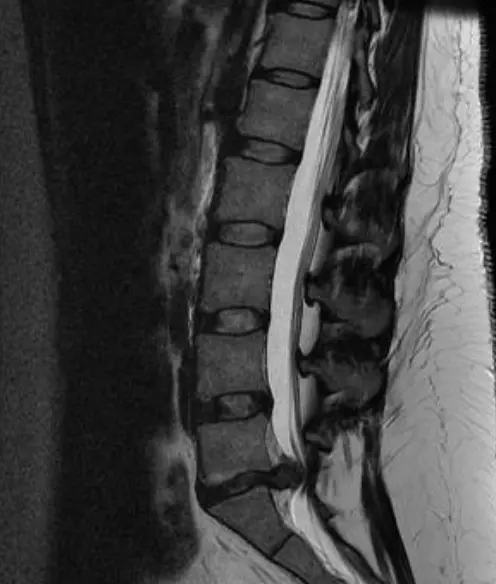

■ MRI (가장 정확한 검사)

추간판의 탈출을 확인할 수 있으며, cauda equina의 압박 소견도 확인할수 있음